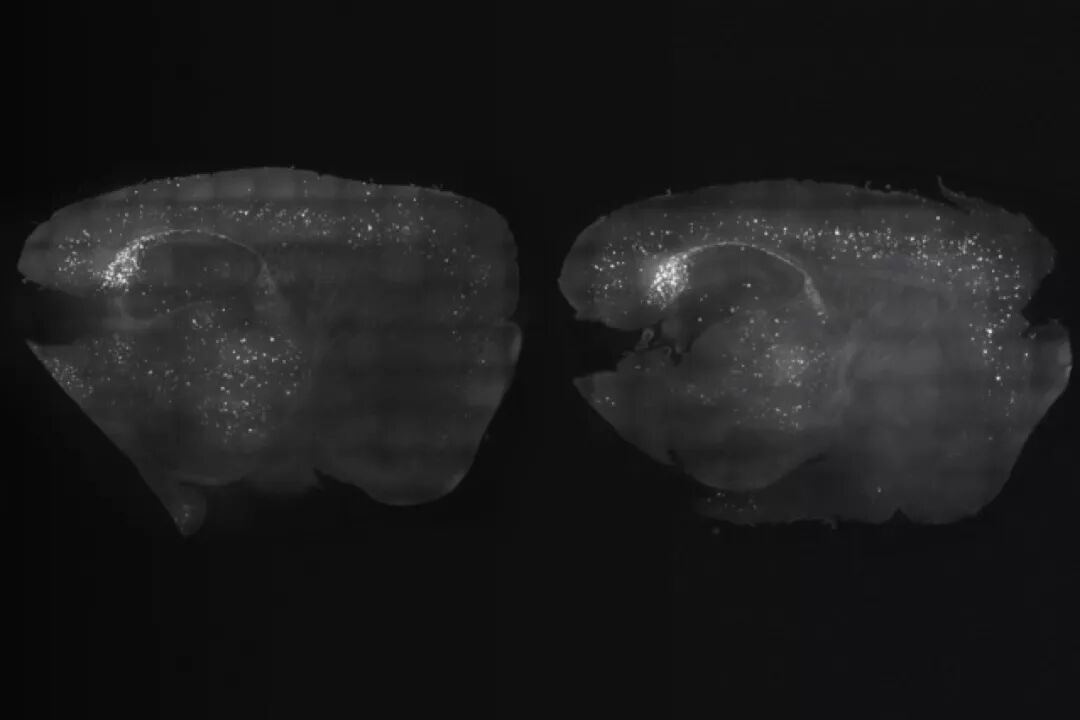

与右侧未治疗的小鼠相比,经过光和声音联合刺激的左侧小鼠皮层淀粉样斑块减少

并且,声音和光的结合进一步扩大了影响范围,在大脑内侧前额叶皮层中也发现了数量增加的小胶质细胞。这些小胶质细胞在蛋白质斑块周围聚集,行使自己的清除功能。联合使用1周后,与没有接受刺激的小鼠相比,前额叶皮层总斑块体积减少了37%,数量减少了34%。